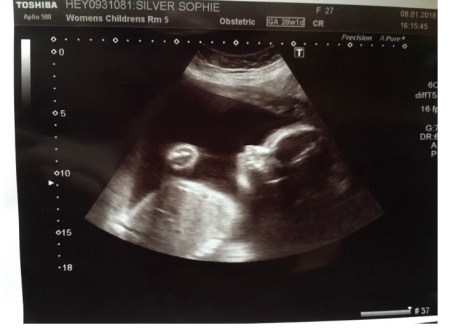

The pregnancy was in no way an easy ride, we were in hospital at least once a week for either fluid scans, growth scans or because of reduced movements. Sophie was carrying a lot of fluid but it was just below the dangerous limit and Henry seemed to be growing quickly, but again he was always below the 90th percentile. Every time we went into hospital we came out feeling reassured with a happy healthy baby kicking Sophie like crazy.

Monday morning I was finishing work before taking my paternity and annual leave, this was it, in my mind, the start of birth. We were both excited and nervous about the induction, but we just could not wait to see our little man. The evening came and we set off to the hospital for induction, nervous and excited we arrived to be put on a monitor just as a formality to check everything was okay. Everything was fine, as usual, our son was asleep at first and it took a while before he moved enough for the midwives to be fully satisfied. We were then called in for the induction and Sophie had a balloon fitted, it was awful to watch as it seemed to be quite painful for her. Although once in everything seemed fine, our boy was moving around and there was no sign of distress.

We went home that evening and it felt like Christmas Eve. We understood that it may take a few days for anything to happen but the midwife told us more often than not it is only the balloon that is necessary in induction. There were multiple kicks during the night and Sophie struggled to sleep at first because of how active he was, they said there would be more movement as we would expect. The movements continued on Tuesday morning until about 11am, Sophie didn’t feel anything, a couple of hours passed and we had tried the regular tricks like they always told us, eat something with high energy, drink and lay down etc. There was still nothing so we went to the hospital, we were due to go only a few hours later to have the balloon removed anyway so we packed the car because we would be staying in and we should be coming home as a family of three.

When we arrived at the hospital we left all of the bags in the car, went to the waiting room and sat in the all too familiar room. We did not wait long before they called us up to the labour ward to be checked, it made more sense to do it there as we would just have to go there after anyway. As Sophie started to get comfortable we remembered we had brought red pillows that were still in the car, to indicate that Sophie was suffering from pelvic girdle pain. As they started to hook Sophie up I went to go and get the pillows. As I returned Sophie and the midwife were walking towards me in the corridor. Sophie said to me, quite calmly, that we had to go downstairs to check as they thought the machine was not working great and could not clearly hear Henry’s heart. She seemed so calm I thought there was nothing to worry about.